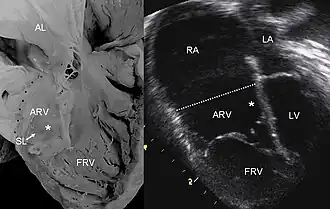

Pathologische hartdoorsnede vergeleken met een echo bij de ziekte van Ebstein.